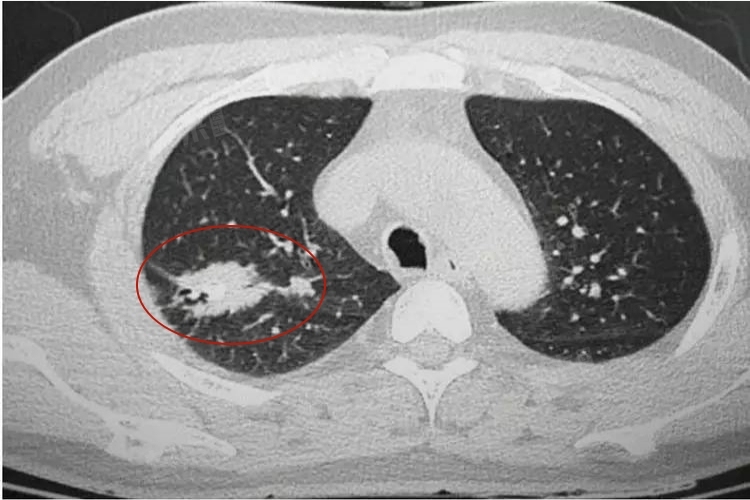

- 在大多数情况下,单纯的肺部钙化通常并不严重。这些钙化灶往往是稳定的,不会对身体造成明显的危害。其虽然存在于肺部,但一般不会影响肺的正常功能。如果肺部钙化同时伴有其他异常情况,就可能需要引起重视。如果钙化灶周围出现了新的病变,如肿块、结节等,或者患者出现了咳嗽、咳痰、咯血、胸痛、呼吸困难等症状,就可能提示存在其他疾病。此时需要进一步进行详细的检查,如胸部CT扫描、支气管镜检查、痰液检查等,以明确病因,并采取相应的治疗措施。

肺部钙化灶的大小和数量对肺功能有着不同程度的影响。如果肺部只有少量的、小的钙化灶,就像散落在肺部组织中的微小颗粒,则一般不会对肺的通气和换气功能产生显著的干扰。因为肺组织具有一定的代偿能力,在小范围的病变情况下,剩余的正常肺组织可以承担起呼吸功能。但如果钙化灶的数量较多,或者钙化灶体积较大,就可能会压迫周围的正常肺组织。